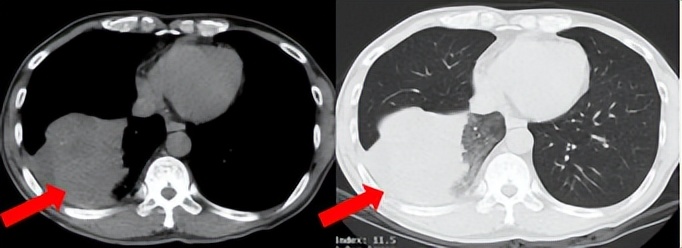

53岁男性,无吸烟饮酒史,脑血栓病史。2024年7月胸部CT:右肺下叶见一团块状软组织密度影,范围约10.8×9.0cm,边界不清,周围并见斑片状磨玻璃密度影,右肺下叶前底段支气管阻塞。纵隔及右肺门见肿大淋巴结影。考虑右肺下叶支气管肺癌。伴纵隔及右肺门淋巴结转移瘤,右下肺静脉瘤栓。2024.7.23行肺穿刺取病理:(肺)腺癌伴有神经内分泌分化。NGS基因检测:RET KIF5B exon15-RET exon12融合。PD-L1(克隆号28-8)TPS=90%。

治疗经过:2024.08开始口服赛普替尼(160mg,bid)。2024.09复查胸CT评效PR。2025.1复查胸CT:右肺下叶外基底段见一不规则形实性肿块,大小约94mm×87mm,边缘呈分叶状,其内密度不匀。右侧胸腔见少许水样密度影。评效PD,PFS=5个月。患者未同意再次组织活检,目前应用卡博替尼治疗,仍在随访中。治疗期间未出现毒性反应。

2024.08

2024.09评效PR

2025.01评效PD